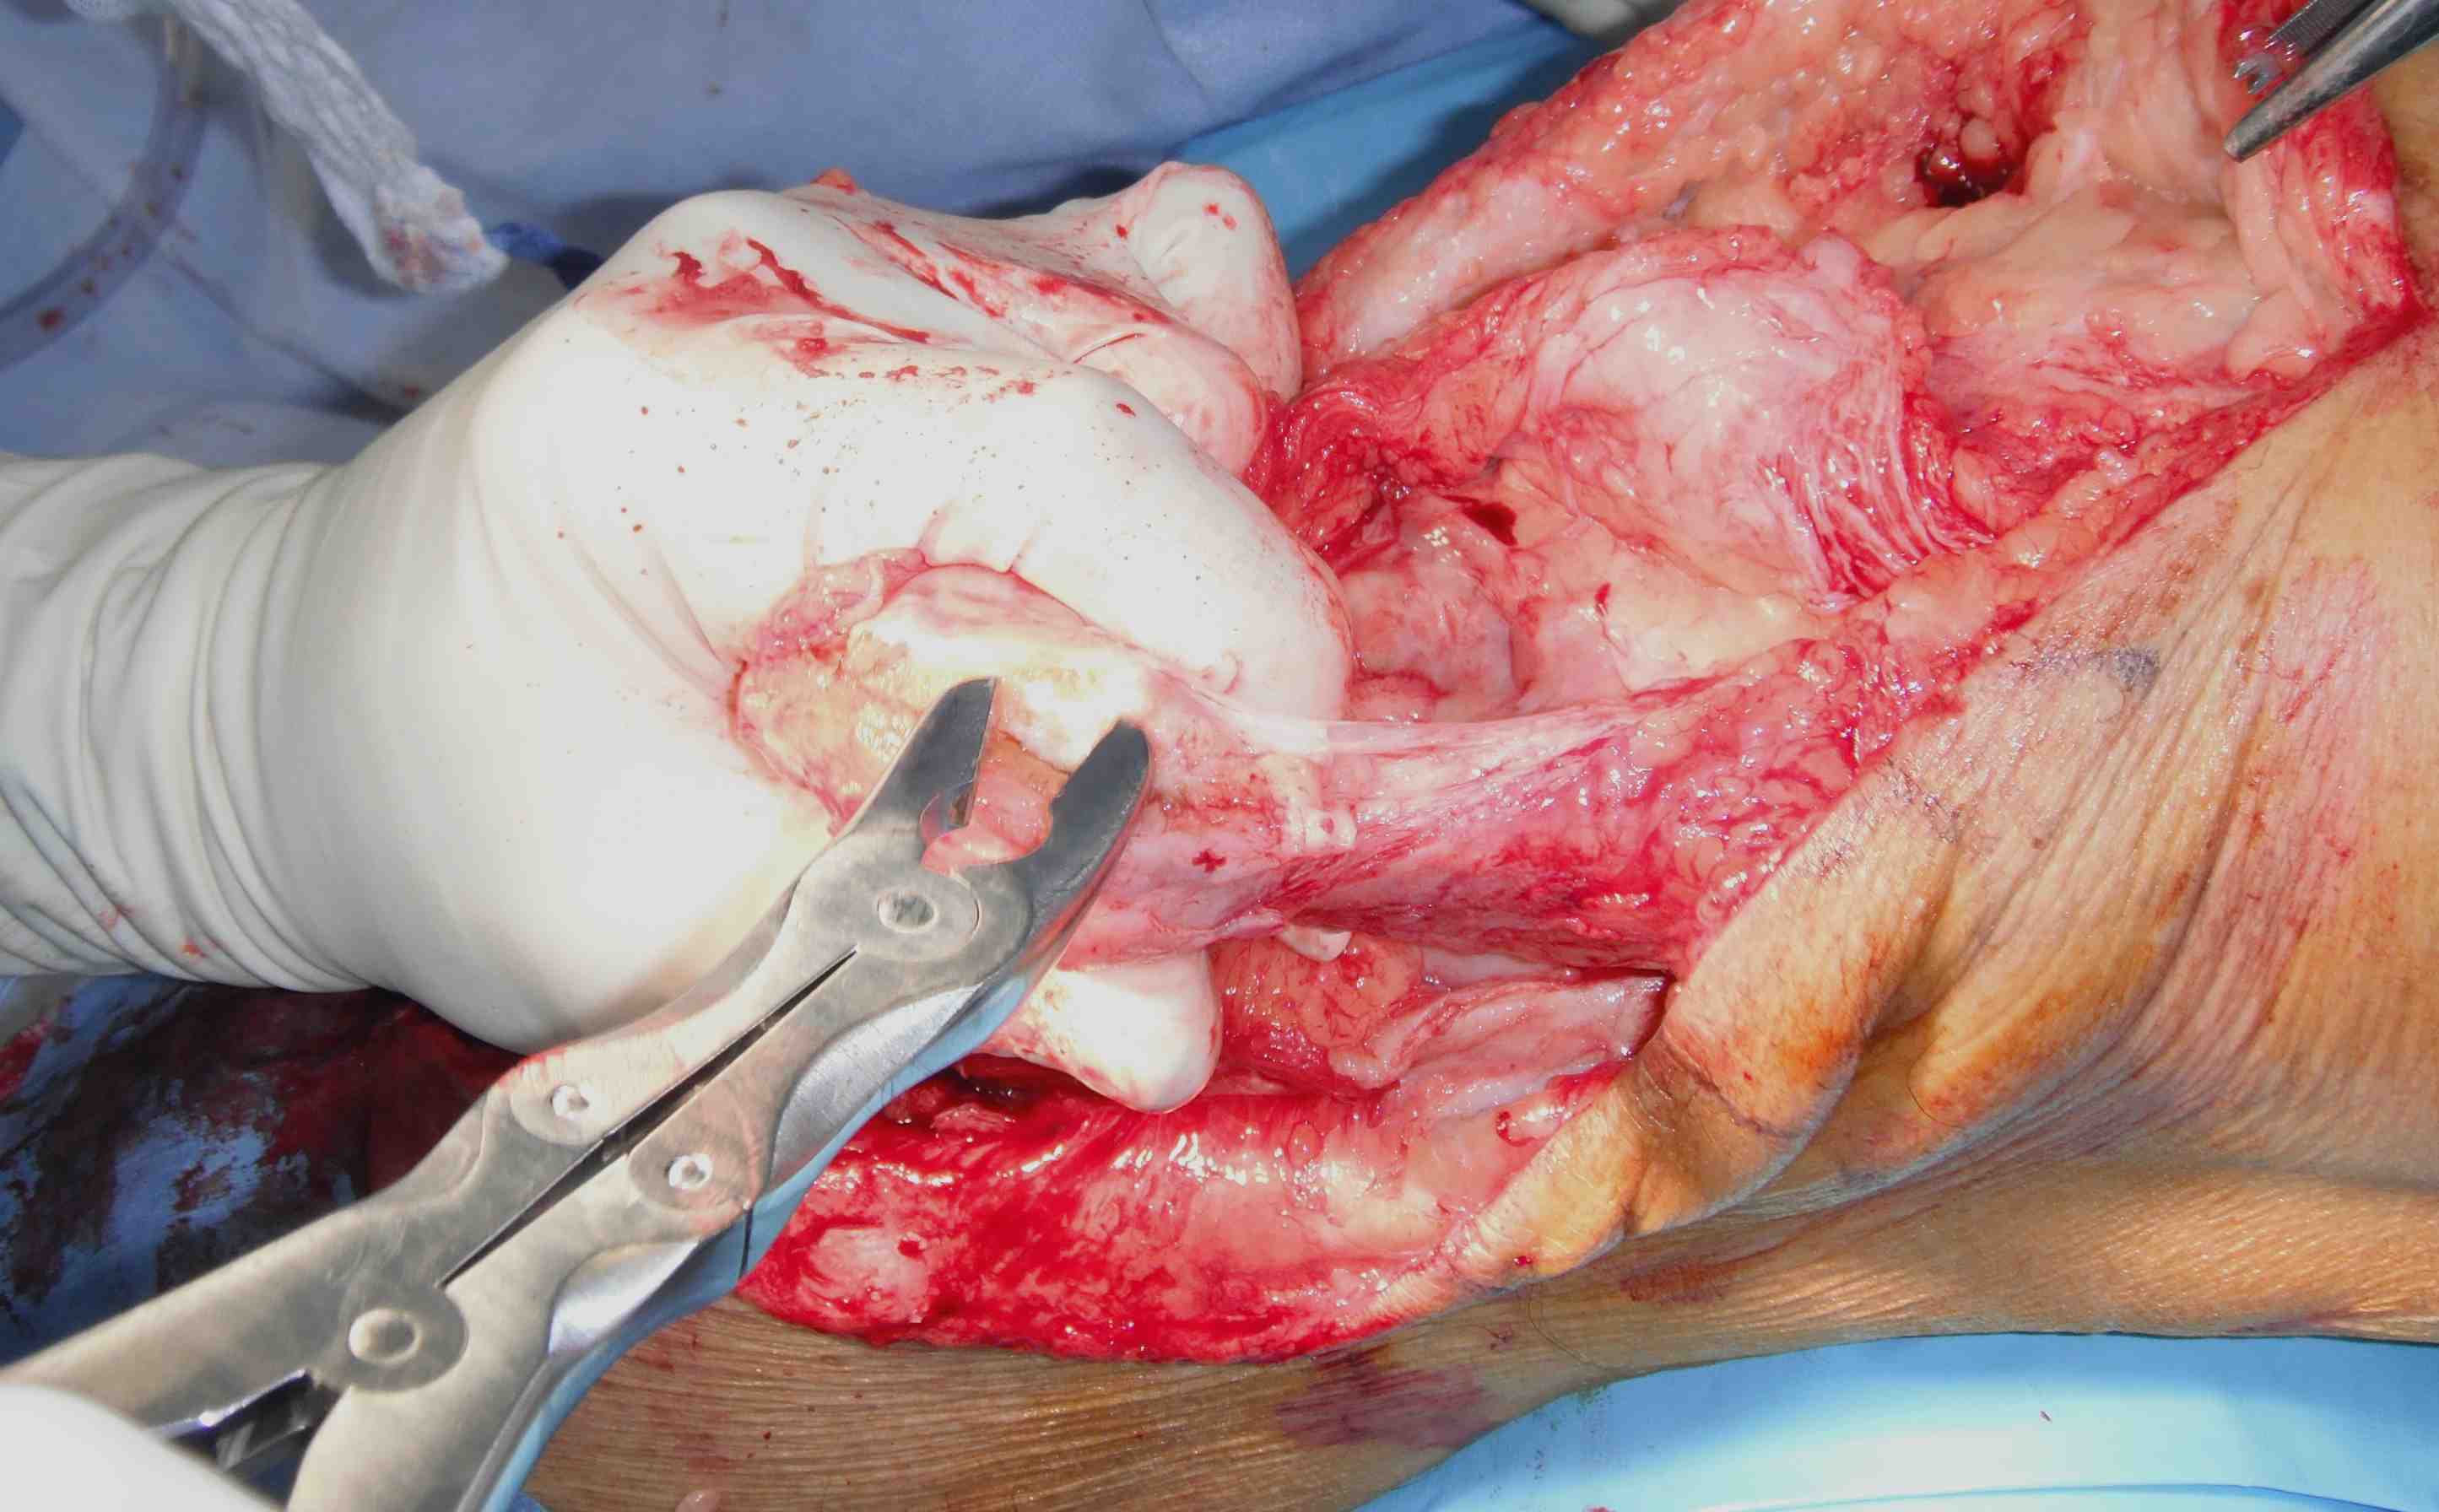

Midline incision

- expose quadriceps

- mobilise tendon / release from subcutaneous tissue

- debride insertion on patella

Drill holes in patella

- pass sutures with houston suture passer

- pass large non absorbable suture

- multiple times through tendon

Other option

- suture anchors in distal patella